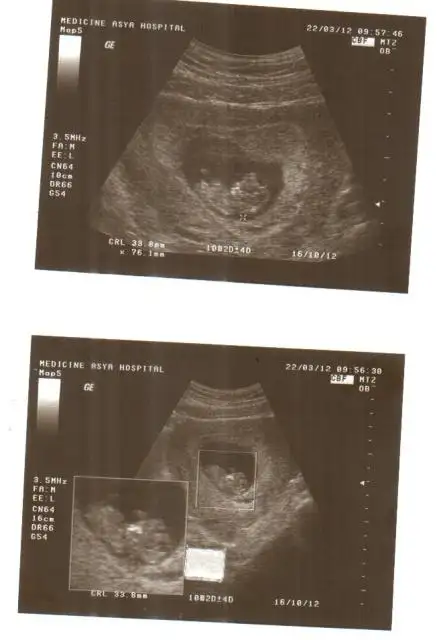

Selam kızlarrrr..Dün çoook güzel bir gündü..Çok şükür muayene süper geçti.İlk kez bu kadar büyük ve ayrıntılı gördüm.kolunu, bacağını,parmaklarını...Sağolsun minnakım annesine kıyak yaptı ve bir türlü yan pozisyonu almadı,hep kafası bize dönük el salladı :) bi 10 dk uğraştıktan sonra tuvalete gönderdi beni dr.geri geldim hala aynı..bi 5 dk. daha dürtükledi falan, yook dönmüyor bir türlü.hareketli ama yan dönmüyor :)

Tüm ölçümlerini aldı.(kan sonuçlarını 1 hafta sonra alıcam).bu arada bayaa birşeye bakıyorlarmış;burun kemiği ölçümü,batın duvarı,mide,böbrekler,mesane...hepsi normal çıktı çok şükür.ense kalınlığı da normal

(5,2 cm olmuş teyzeleri.sat la da uyumlu ayrıca)

bu arada kızlar ultrason resimlerinizi koysanıza bakalımhatta topik açılsa göbişler ve ultrason resimleri ile ilgili çok iyi olur